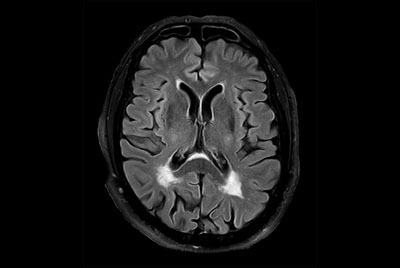

Multiple Sclerosis versus TIA

Brain Multiple Sclerosis

FLAIR* protocol for Multiple Sclerosis